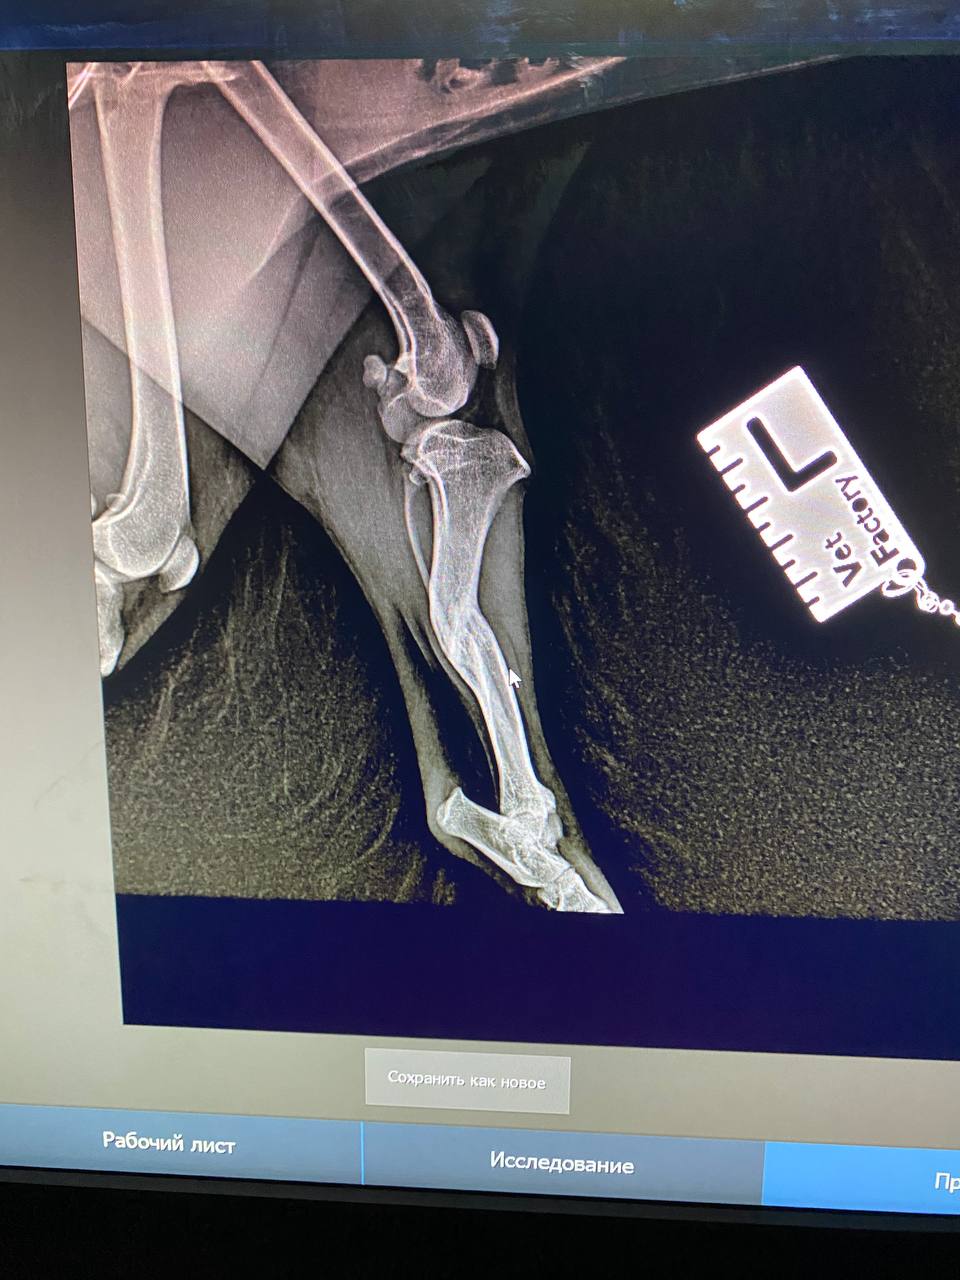

Сходили к ортопеду, у Люси перелом лапы в трех местах, уже сросшийся. Предлагают операцию в 2 этапа.

Завтра с Люсей едем на повторную консультацию в Колпино. У нее пока течка, отложили немного с ногой вопросы, не горит уже, срослось все вкривь и вкось(

вот это перелом...она не под машину или какой транспорт попала, интересно. У нее получается в нижнем переломе верхняя часть кости срочлась с серединой нижнего обломка?

Похоже, что под машину. Когда ее нашли, видимо, свежий был перелом. Но пока волонтеры там мумили, хотя мы сразу согласились забрать, срослось все наперекосяк(Анастасия Нибелунг писал(а): ↑10 апр 2026, 20:33 вот это перелом...она не под машину или какой транспорт попала, интересно. У нее получается в нижнем переломе верхняя часть кости срочлась с серединой нижнего обломка?

Возможно будет 3 этапа операций, поскольку у Люсьенки по КТ стало понятно , что еще повреждена голень, вывернута неестественно вправо.